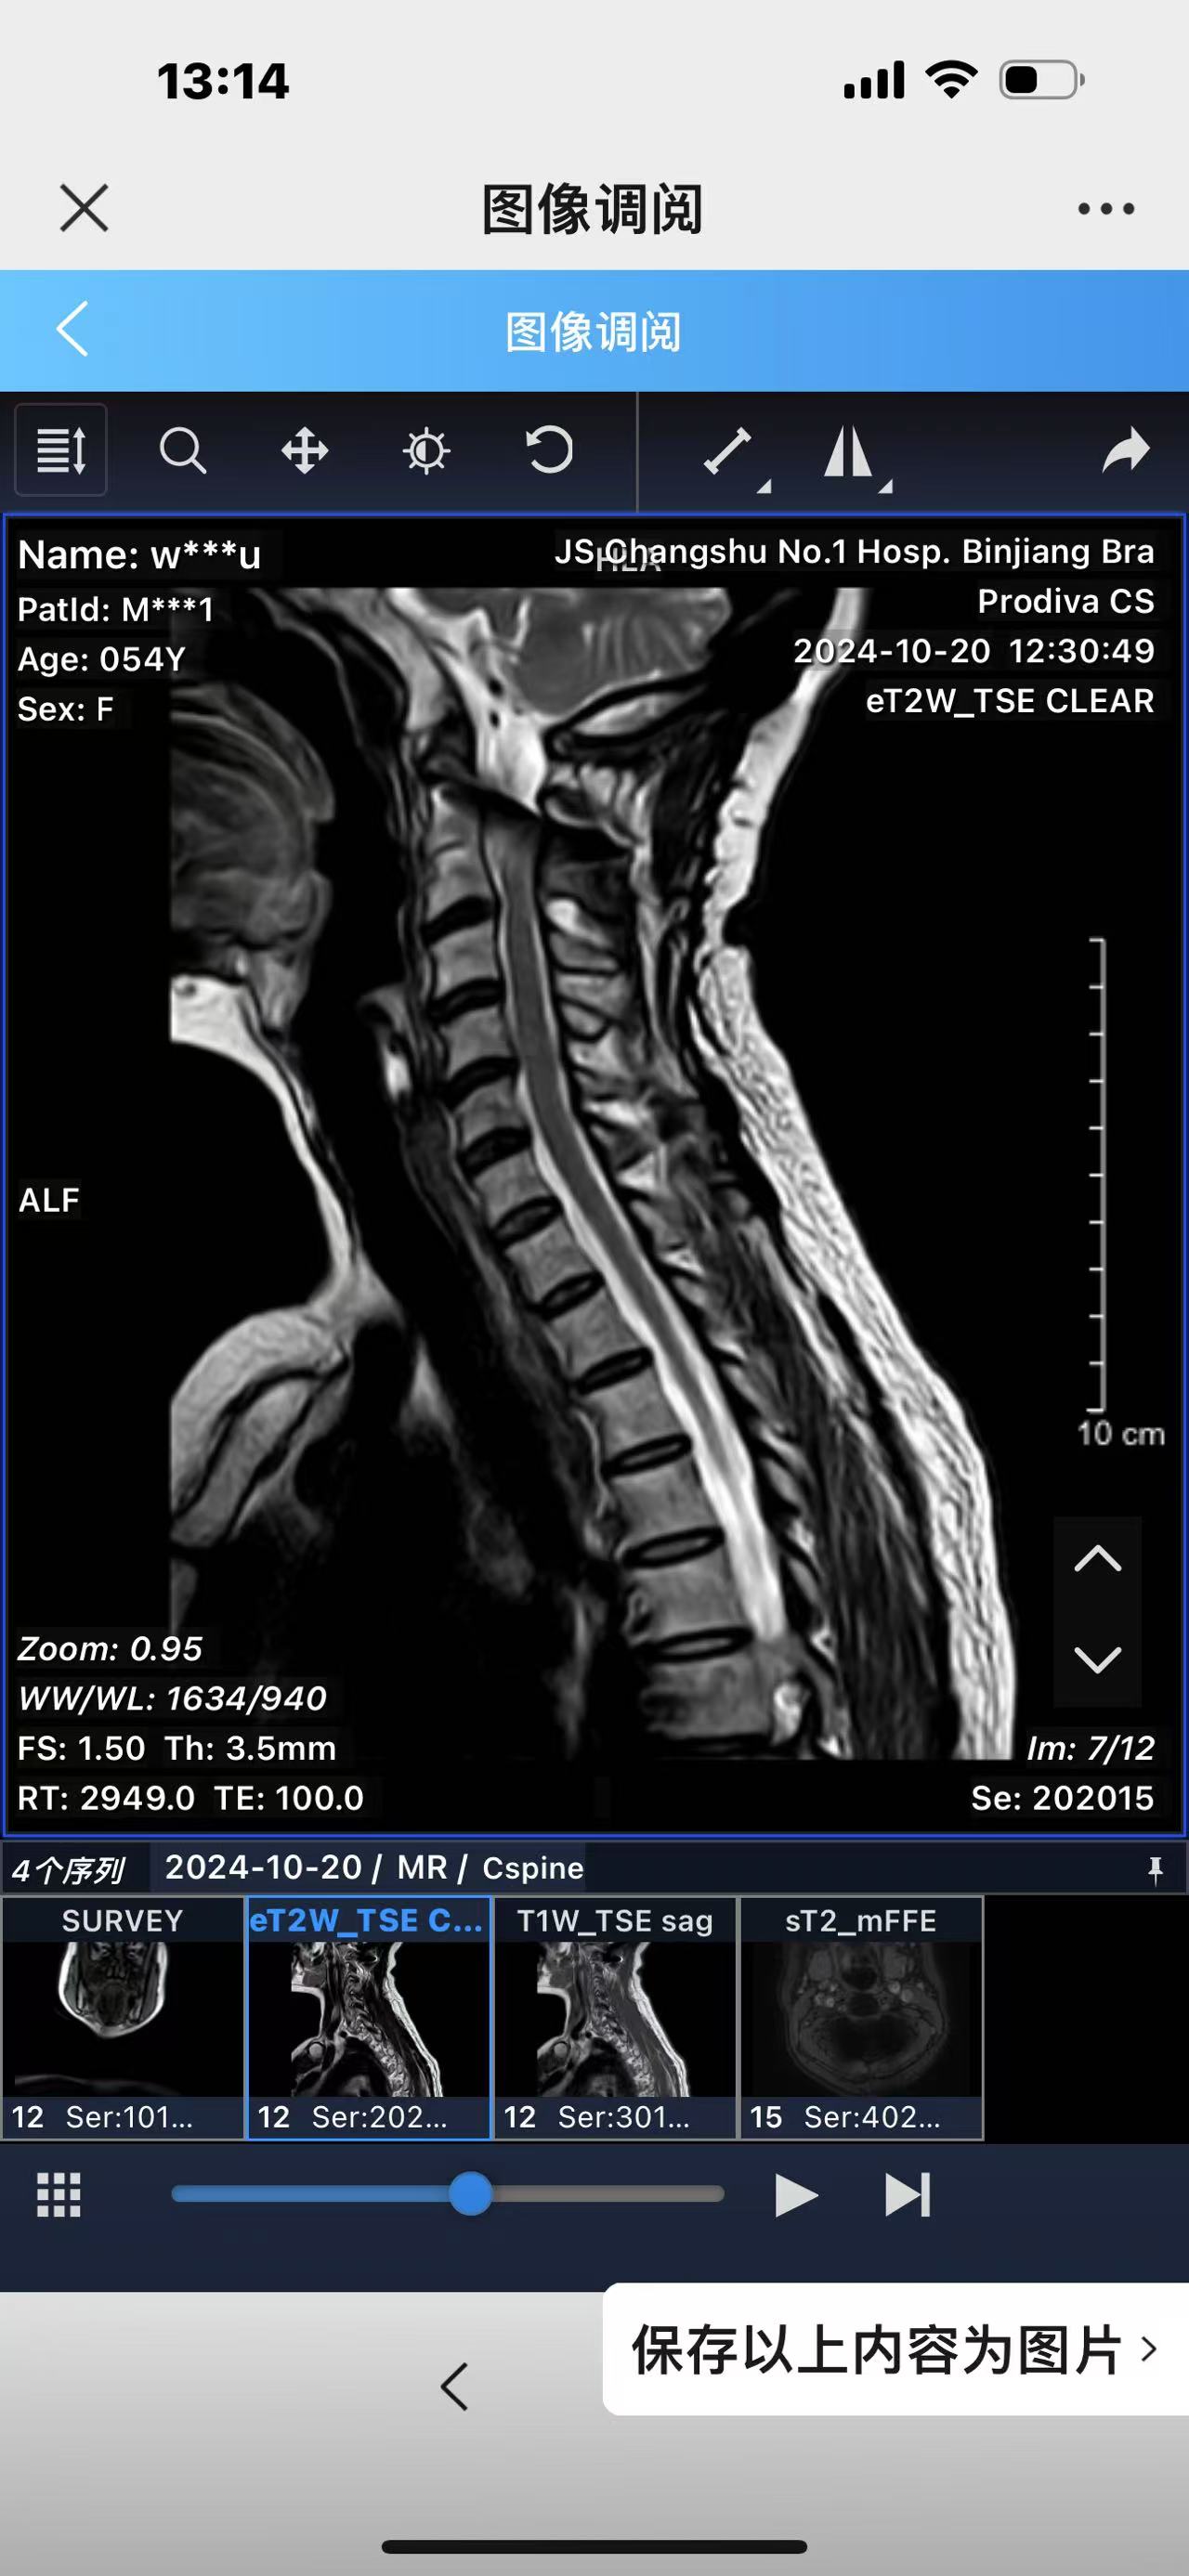

• 诊断:寰枢椎脱位,颅底凹陷

• 术后影像:

• 2024.10.20,复查,对位良好,偶尔会肩甲骨酸,坐下就不酸。